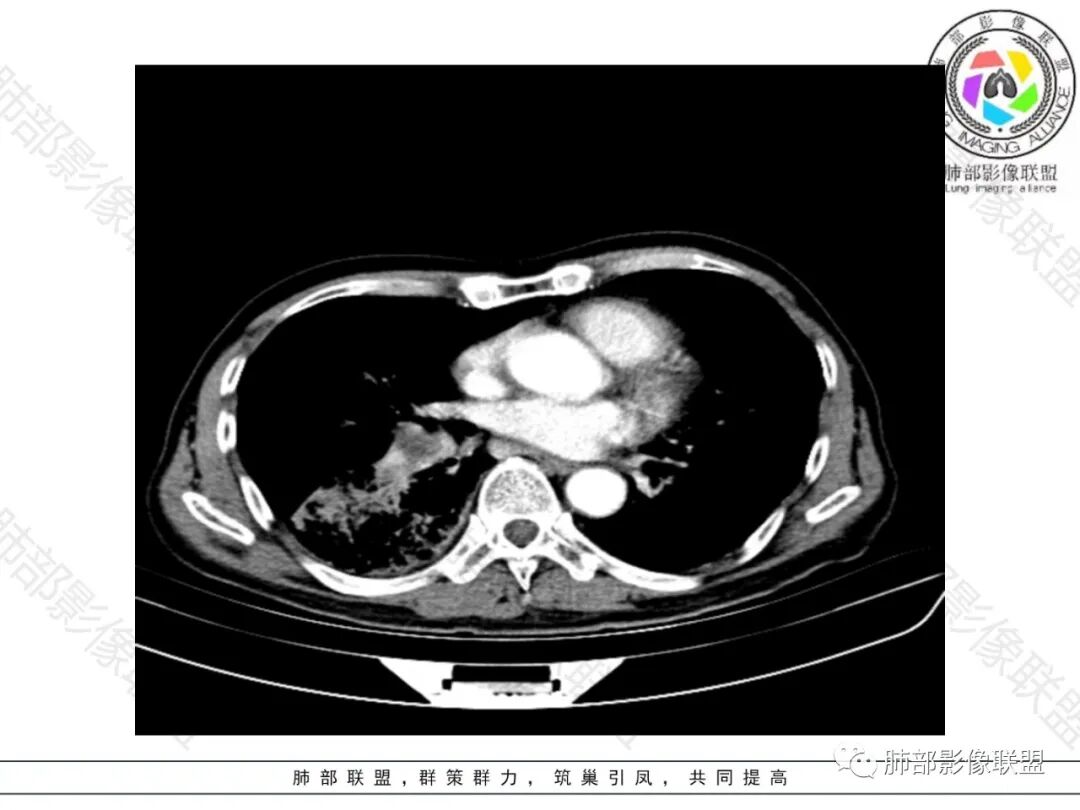

双肺慢支肺气肿。右肺下叶大片状影,支气管狭窄,枯枝状。间杂网格状影,实变影(与胸膜糊墙),叶间裂膨隆。右肺门增大。增强后右下肺片状影内血管束失去正常形态,边缘模糊。实变影不均匀强化。纵隔及右肺门多组淋巴结肿大,其中右侧10、11、12组淋巴结肿大内见液化。考虑肺炎型肺癌并感染?不典型结核待除外。左下小片影?(层面不全)。

右肺下叶大团块影,斜裂膨隆,内支气管破坏,纵隔窗实质性成份少有强化(假大空),肿瘤CA125、199高,考虑粘液腺Ca右肺门淋巴结及纵隔淋巴结大,右肺下动干起始处充盈缺损(示栓塞或Ca栓;余肺叶弥散网格状改变,间质增厚及纤维化表现!

老年男性,反复咳嗽咳痰喘憋8年,加重10天,发热半天。白细胞计数明显升高(存在细菌感染可能),CEA、CA19—9升高(肺癌或间质性肺疾病引起可能)。痰培养见肺克。CT;双肺弥漫小叶间质、中轴间质增厚,胸膜下肺气肿,右肺门及右下叶可见实变影,边界模糊,内支气管走形僵硬,部分见蜂窝样改变,增强后实变区可见低密度区(粘液?),叶间裂膨隆,纵隔及右肺门见肿大淋巴结,右肺门淋巴结内见坏死。存在感染,但单纯感染难以解释支气管走行僵硬、实变内的低密度病灶,考虑恶性伴感染,肺炎性肺癌或黏液腺癌。

整个背景是一个肺气肿并间质纤维化,肺气肿以上肺为主(有些地方分不清到底是小叶中心或间隔下肺气肿伴间隔增厚还是蜂窝),左肺下叶正常结构消失,以弥漫网格为主,应该没有多少正常肺功能组织。右肺下叶肺动脉栓塞,再往下几层应该是肿大淋巴结并坏死。右肺下叶的病变考虑粘液性腺癌, 需与感染鉴别(有没有可能是肺梗死呢?)

慢阻肺背景,右下肺外周胸膜下实变影伴内部细网格征,实性部分强化弱,右侧肺门淋巴结肿大并内部坏死。

2.影像表现:肺气肿背景,右肺下叶呈现明显网格影及蜂窝影、枯枝征,边缘膨隆、叶间裂向前方推移。病灶密度不均,前份见不规则片状实性密度区,实性部分轻度强化,边界不清,周边特征掩盖不清。支气管主要分支显示,呈枯枝征。纵隔窗病灶密度偏低,病灶内血管影边缘稍显模糊,未见明显液化坏死区。

右侧肺门淋巴结肿大,中央低密度;纵隔见轻度增大淋巴结。

3.综合分析:临床方面:慢性病程、急性发作,呼吸道症状伴发热,炎性指标升高,提示存在感染可能;CA199升高,但相对特异性不高。影像双肺气肿,右肺下叶蜂窝状改变明显,夹杂实变密度区,支气管相关但未见阻塞,较常见于感染性病变,如G-杆菌感染等。蜂窝影什么时候出现我们不得而知,实变区周边特征掩盖不清。

前后三月余病灶变化不明显,右肺门异常肿大淋巴结让人警惕恶性病变可能性。